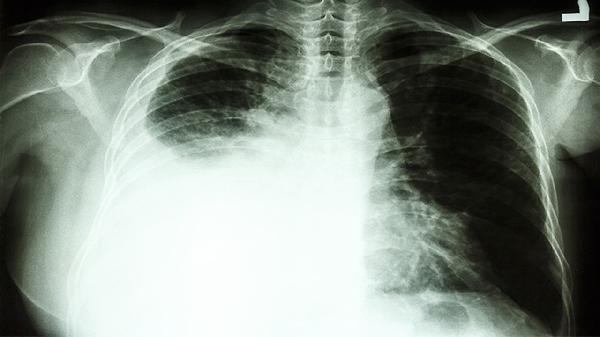

肺癌是一种恶性肿瘤,主要发生在肺部,治疗方式需要根据病情严重程度、肿瘤类型和患者身体状况综合决定。手术治疗适用于早期肺癌患者,通过切除肿瘤组织达到治疗目的。放射治疗利用高能射线杀死癌细胞,适用于无法手术的患者或术后辅助治疗。化学治疗通过药物杀死癌细胞,常用于中晚期肺癌或术后辅助治疗。靶向治疗针对特定基因突变的肺癌患者,能够精准攻击癌细胞。免疫治疗通过激活患者自身免疫系统对抗癌细胞,适用于部分晚期肺癌患者。